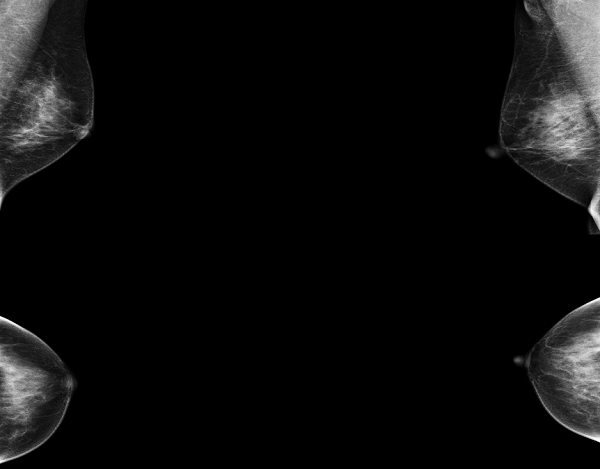

图2 患者A的超声表现图:(粗箭头处)乳腺囊肿,表现为无回声区;(细箭头处)乳腺实性结节,表现为低回声